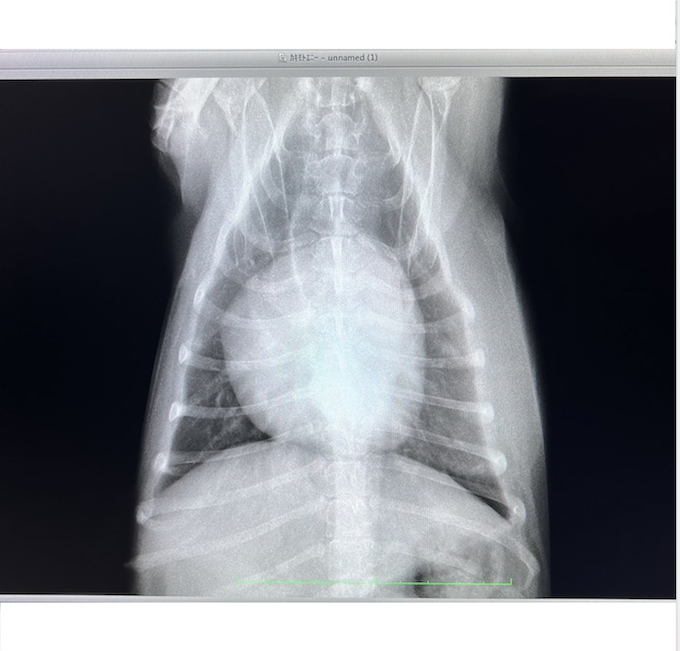

僧帽弁閉鎖不全症からくる肺水腫で

地元動物病院 K先生の

夜間診療へ駆け込み即入院。

※動物病院の先生に資料掲載許可を得ています

【2022年6月22日】

2度目の肺水腫を起こし

またもK先生の病院へ運び込みます。